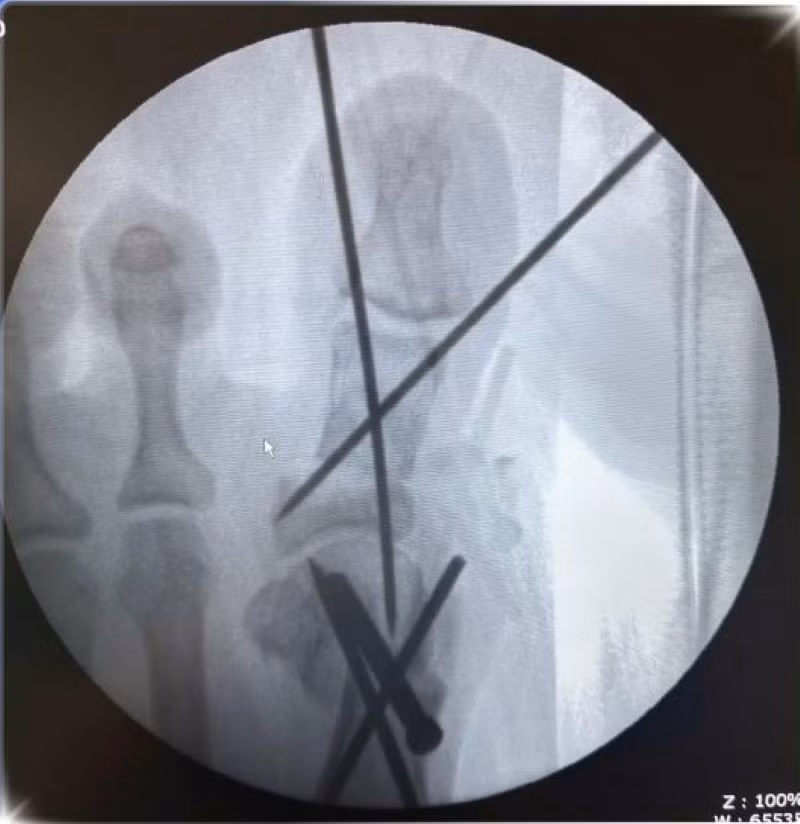

Ca phẫu thuật được tiến hành dưới sự hỗ trợ của hệ thống C-arm, thiết bị chẩn đoán hình ảnh trong mổ, giúp bác sĩ xác định chính xác vị trí cần can thiệp. Quá trình bao gồm: cắt xương, nắn chỉnh trục ngón cái, cố định bằng đinh và vít, sau đó khâu đóng và băng ép vết mổ.

chan-cai-2.jpg

Hình ảnh cận lâm sàng - Ảnh BVCC